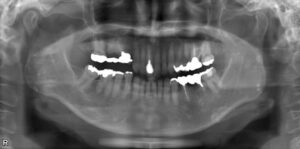

大臼歯2本欠損症例

BEFORE AFTER 43歳女性/上下2本欠損/インプラント埋込手術 【治療内容】 右上第二大臼歯の被せ物が外れてし…